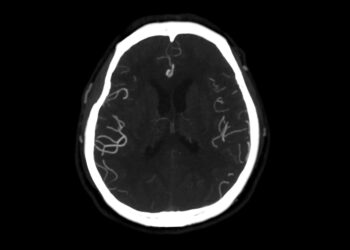

Paveldima hemoraginė teleangiektazija (HHT), dar vadinama Oslerio–Weberio–Rendu sindromu, yra reta genetinė liga, kuri pažeidžia kraujagysles. Šios ligos metu organizme formuojasi...